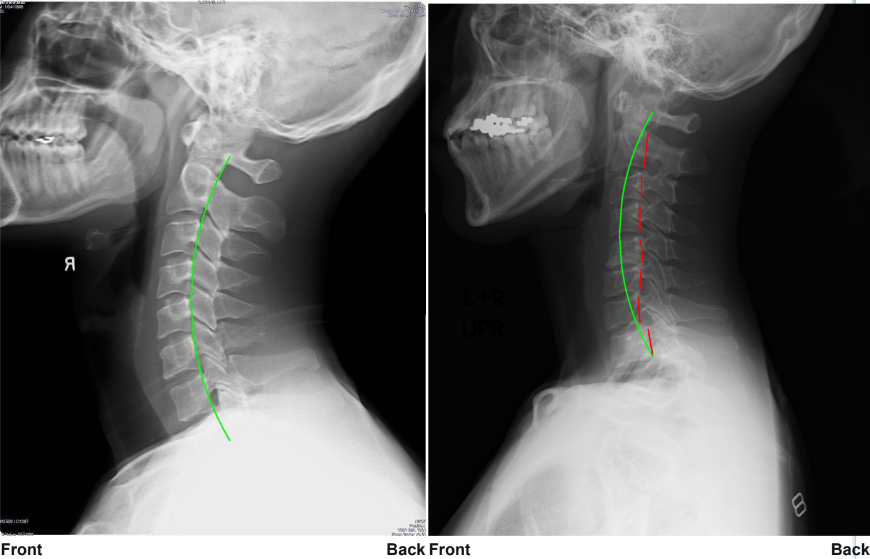

【実際の写真】

解説:左写真が理想的なライン。右写真の赤い部分から、ストレートネックであることが分かる

CBPによるレントゲン分析は、理想的な骨の位置からのズレを数字で見られるのが特徴です。

「歪んでいるね」などの漠然とした診断ではなく、エビデンスに基づいた診断。

患者の立場としても納得できるものでした。